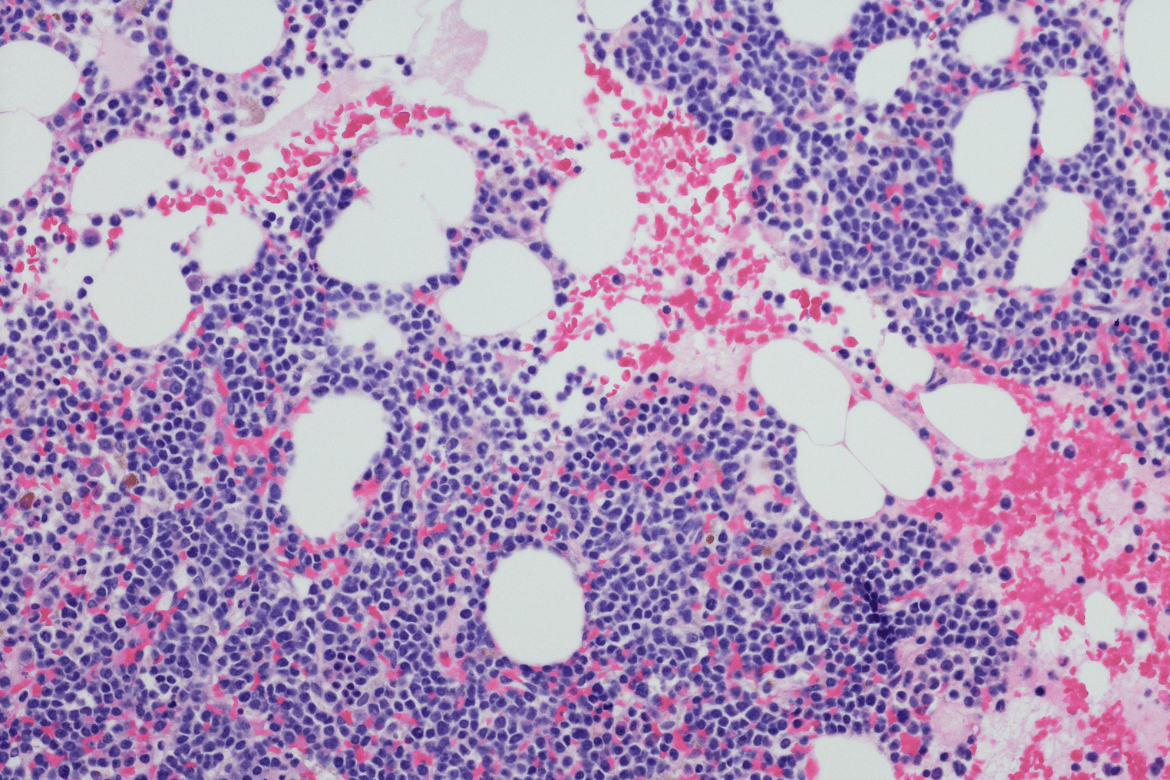

Normalmente, las células plasmáticas -o “linfocitos de tipo B” maduros- se encuentran en la médula ósea. La médula ósea es el tejido blando dentro de los huesos. Además de las células plasmáticas, la médula ósea contiene también otras células sanguíneas, como los glóbulos rojos, los glóbulos blancos y las plaquetas.

En este cáncer, las células plasmáticas de la médula de los huesos que normalmente producen anticuerpos, sufren mutaciones y se reproducen descontroladamente, generando un exceso de inmunoglobulinas anormales o anticuerpos tipo M, y una disminución de otros glóbulos blancos y de los glóbulos rojos.